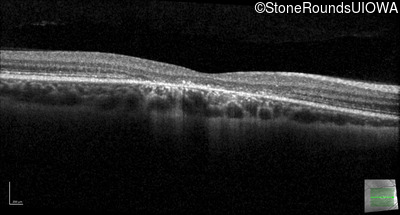

Optical Coherence Tomography - Right - 20/50 -1

Exemplar / OCT Stack